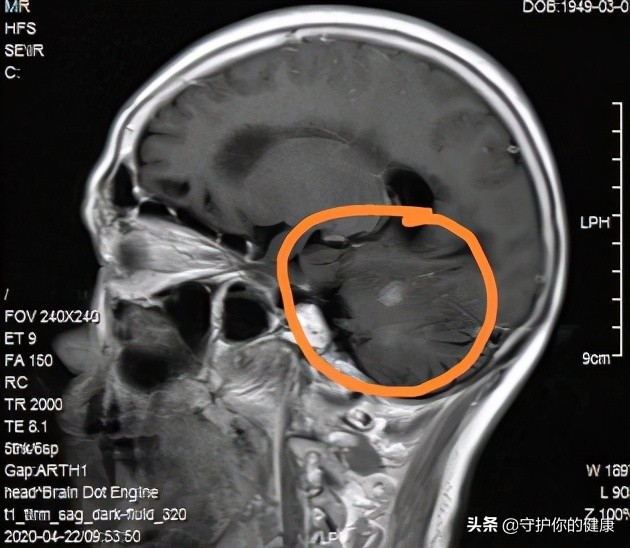

这是靶向治疗前的脑部磁共振(图一):

图一:

吃药前

两图对比肿瘤是明显缩小的。